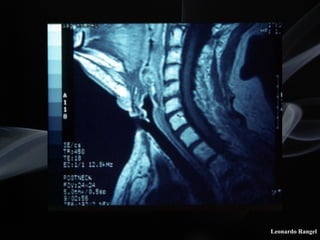

!Vídeo-laringoscopia

!Tomografia computadorizada

!Ressonância magnética

LPSC

avaliação da extensão

tumoral